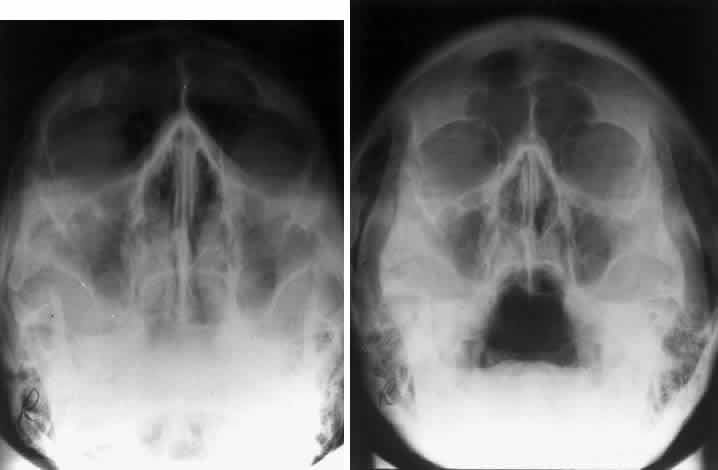

BASAL PROJECTION (SUBMENTO-VERTEX)

The basal projection (Fig. 5) for the evaluation of the sphenoid sinus and skull base was described initially by Arthur Schuller12 in 1905 and later popularized in this country by Bowen.13 This projection is obtained with the patient's neck extended either in the supine or upright position. The top of the head is placed so that the infraorbitomeatal line is parallel with the x-ray cassette. The x-ray beam is directed at right angles to the infraorbitomeatal line.5,6 This view shows the lateral walls of the orbit and maxillary sinuses well. The nasopharynx, pterygoid plates, pterygopalatine fossa, and the sphenoid and ethmoid sinuses may also be inspected. Because of the extreme head position, any history of a neck injury is a contraindication to this radiologic study.

Fig. 5. A. Schematic showing positioning for a basal projection. (CR, central ray; IM, infraorbitomeatal line) B. Radiograph of a basal projection. (a, zygomatic arch; b, orbit; c, lateral orbital wall; d, posterior wall of maxillary sinus; e, pterygoid plate; f, sphenoid sinus) (A; Rao VM, Gonzalez CF: Plain film radiography and polytomography of the orbit. In Gonzalez CF, Becker MH, Flanagan JC [eds]: Diagnostic Imaging in Ophthalmology, pp 1–7. New York, Springer Verlag, 1986)